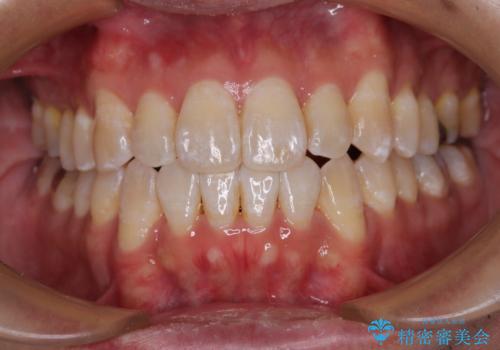

上下の八重歯とクロスバイト ワイヤー装置での抜歯矯正

- 八重歯とクロスバイトを気にして来院された患者様です。

上下ともに八重歯が顕著であり、前歯のクロスバイトがあったため、上下左右の第一小臼歯4本を抜歯し、ワイヤー装置での抜歯矯正を行うこととしました。

前歯の歯列が整ったことで、歯磨きが大変やりやすくなり、患者様には大変満足していただけました。